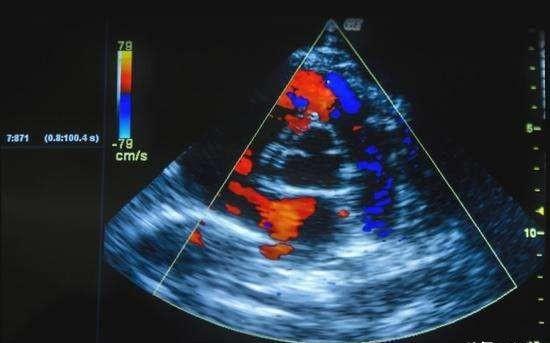

绝大多数人对心电图都很熟悉,毕竟是体检常规项目。并且以为查了心电图没问题,心脏就没问题了,这个是错误的认识。其实心脏彩超对心脏的检查作用更加重要,号称心脏科医生的一只眼睛。

心脏好比是一座房子,有四个房间,左心房、左心室、右心房、右心室,房间之间有墙相隔,即房间隔、室间隔。每个房间都有门,即心脏瓣膜。血管是各种水路管道,心脏内的神经是各种电路管道。心脏的神经传导也就是电路是否异常是通过心电图来反应,心脏血管的异常可以通过冠脉造影或者CTA来确定。而房子的结构和功能是否异常需要通过心脏彩超来确定。

首先我们可以通过心脏彩超了解心脏整体的结构,包括心房、心室的大小,室壁的厚度,还有心脏的阀门即瓣膜有没有关闭不全,有没有狭窄。心包里边是否有积液或者心包是否有填塞,可以进行一个初步的判断。其次心脏彩超可以直观看到心脏收缩功能,室壁运动分析,运动是否协调等。可以通过计算得到心脏的每搏输出量等具体各个数值,对心脏功能进行有效的评估,即通常所说的射血分数,通过射血分数,来判断心脏功能不全的程度。

心脏彩超在临床发挥巨大的作用,操作简便,无辐射,无创伤,无需造影剂,可以重复做并在床旁进行。